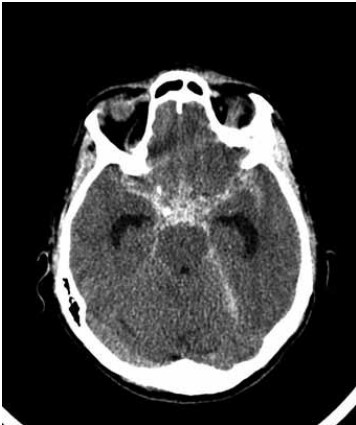

Paciente do sexo feminino, de 48 anos de idade, é trazida ao pronto-socorro com cefaleia e rebaixamento do nível de consciência. Foi submetida à tomografia computadorizada de crânio que evidenciou o achado a seguir:

(Arquivo pessoal; imagem usada com autorização)

Assinale a alternativa correta sobre esse caso.